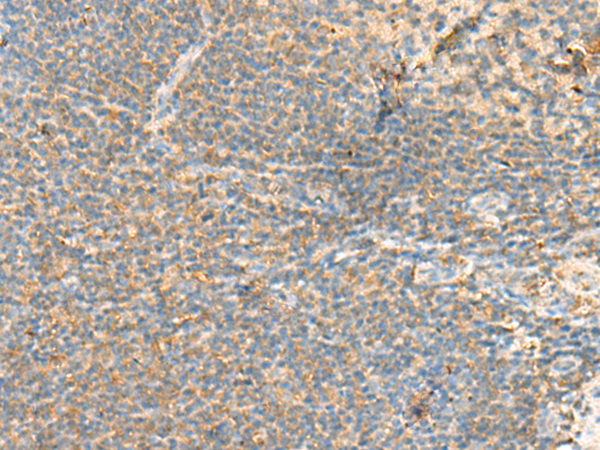

分类: 科研抗体货号: P09870别名: BCM1; BLAST; hCD48; mCD48; BLAST1; SLAMF2; MEM-102应用: WB,IHC反应种属: Human